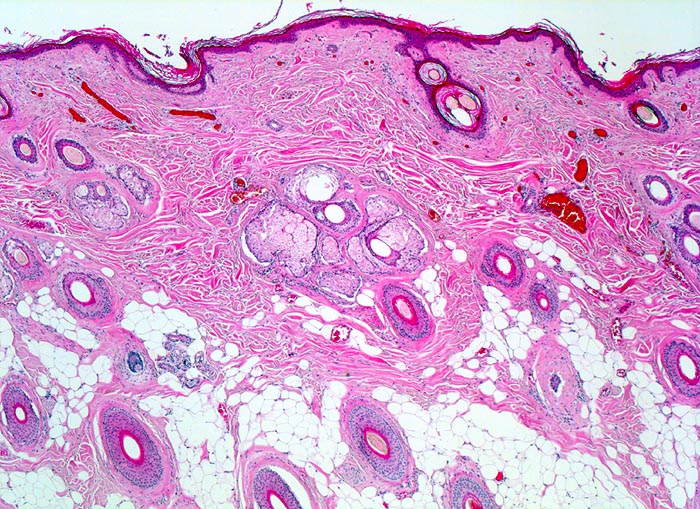

• Symmetrischer leicht exophytischer Tumor.

• Die Tumorzellen bilden Nester in der Epidermis und in der Dermis (=dermoepidermaler bzw. compound Naevus).

• Oberflächliche Tumorzellen enthalten teilweise körniges braunes Melaninpigment.

• Angrenzend an die pigmentierten Zellnester sind Melanophagen erkennbar, deren Zytplasma mit Melaningranula angefüllt sind.

• Die oberflächlichen Naevuszellen zeigen reichlich helles, teils pigmentiertes Zytoplasma und helle ovale Kerne mit kleinen, deutlich erkennbaren Nukleolen. Zur Tiefe hin werden die Naevuszellen kleiner, haben weniger Zytoplasma und dunkle kleine Kerne ohne gut erkennbaren Nucleolus. Die Zellnester werden zur Tiefe hin ebenfalls kleiner (=Ausreifung).

• Keine Mitosen, keine Zellatypien.